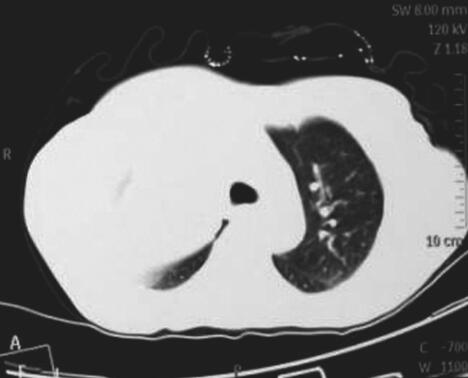

图2肺部CT

右肺上叶软组织肿块影;左肺下叶后基底段软组织影,边缘模糊